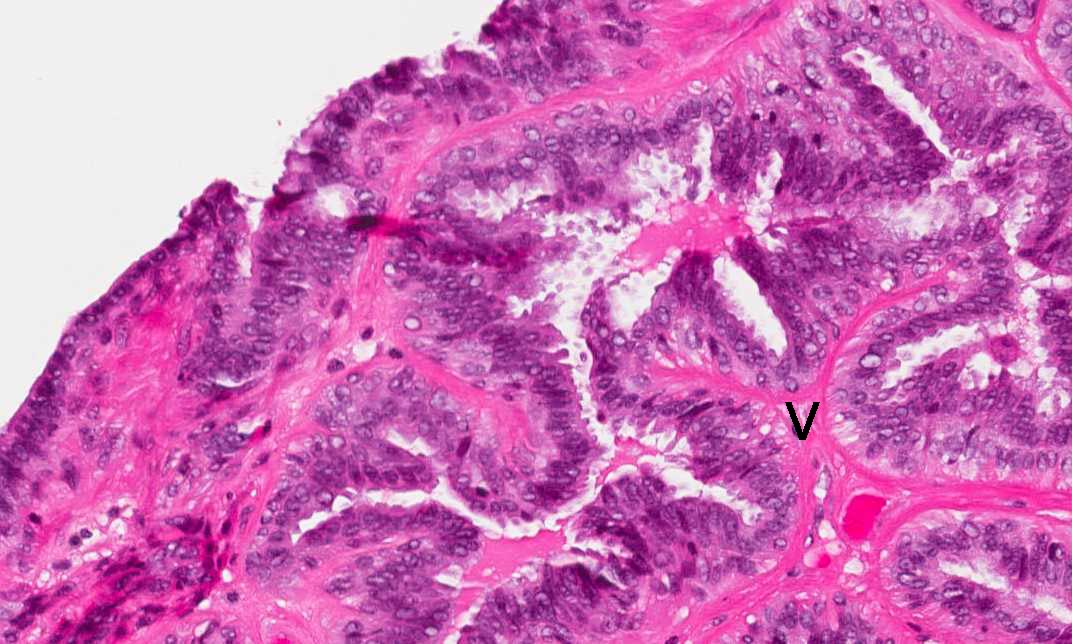

Area 2: Note the papillary, finger-like fibrovascular core (v) that that supports the epithelial cells. There is only one single layer of lining epithelial cells.